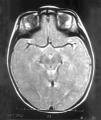

Las exploraciones complementarias realizadas fueron normales: hemograma, bioquímica sérica elemental, creatinfosfocinasa, ácido láctico, piruvato, aminoácidos en suero, ácidos orgánicos en orina, ácidos grasos libres en plasma, carnitina sérica total, carnitina libre, acilcarnitina, cociente acil/libre, equilibrio acidobásico, amonio, hormonas tiroideas, cariotipo, citoquímica de líquido cefalorraquídeo, electromiograma y velocidad de conducción motora de nervio peroneo, biopsia de músculo con estudio estructural, histoquímico y de cuantificación de enzimas de la cadena respiratoria mitocondrial, estudio del ADN mitocondrial de músculo en búsqueda de las mutaciones T8993G, T8993C y A9176C, deleciones únicas o múltiples y depleción por Southern blot, test de edrofonio, estudio de potenciales evocados auditivos del tronco cerebral y una tomografía computarizada (TC) craneal (fig. 1). Se realizaron tres estudios de resonancia magnética (RM) craneal a los 7, 9 y 15 meses de vida que mostraron alteración en la intensidad de la señal en tegmento mesencefálico, pontino y bulbar, más marcado en regiones dorsales (figs. 2 y 3).

Figura 3.RM craneal: secuencia ponderada en T2 a nivel bulbar. Hiperintensidad de la señal del tegmento paramediano bulbar.